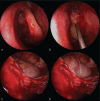

Interventions: We performed endoscopic sinus surgery, which included uncapping of the anterior and superior wall of the mucocele.

Outcomes: The mucocele was treated safely and effectively without touching the medial orbital wall.

Lessons: Clinicians should note that minimally invasive surgery to remove ethmoid mucoceles is relatively straightforward and can prevent the various complications associated with these lesions.